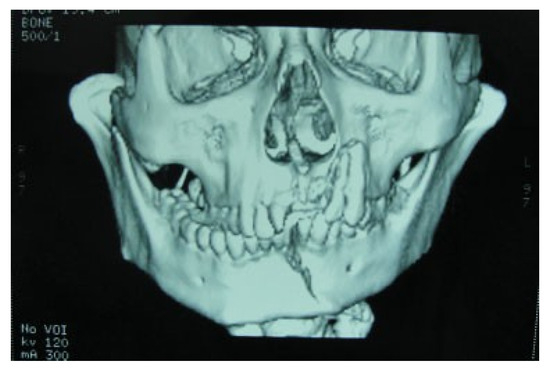

Superolateral Dislocation of Bilateral Intact Condyles—An Unusual Presentation: Report of a Case and Review of Literature

:1. Case Report